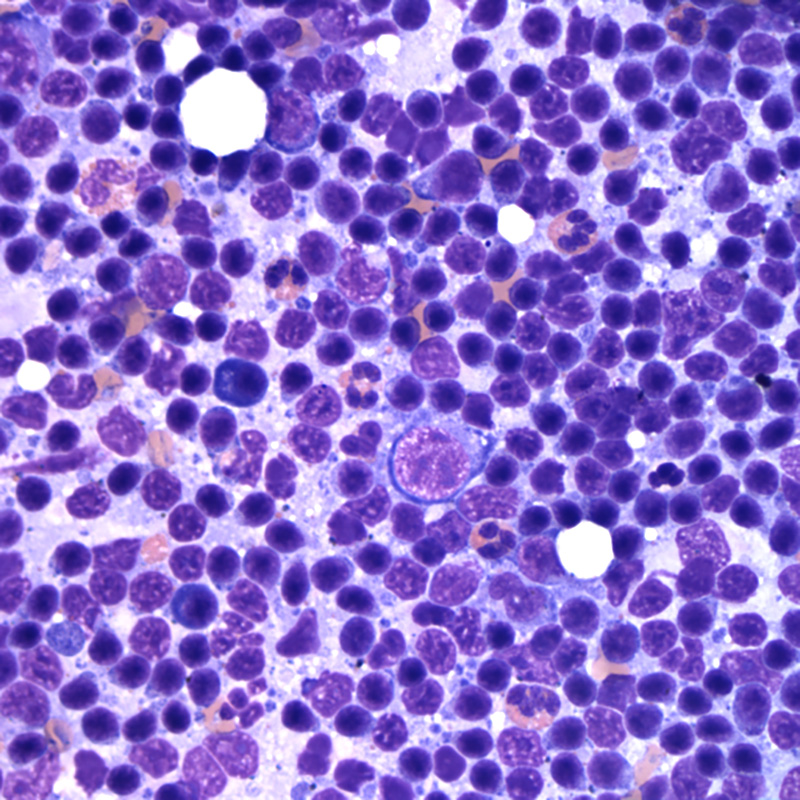

Микропрепараты: Лимфогранулематоз и Нодулярный Склероз

Раздел: Секреты мастерства